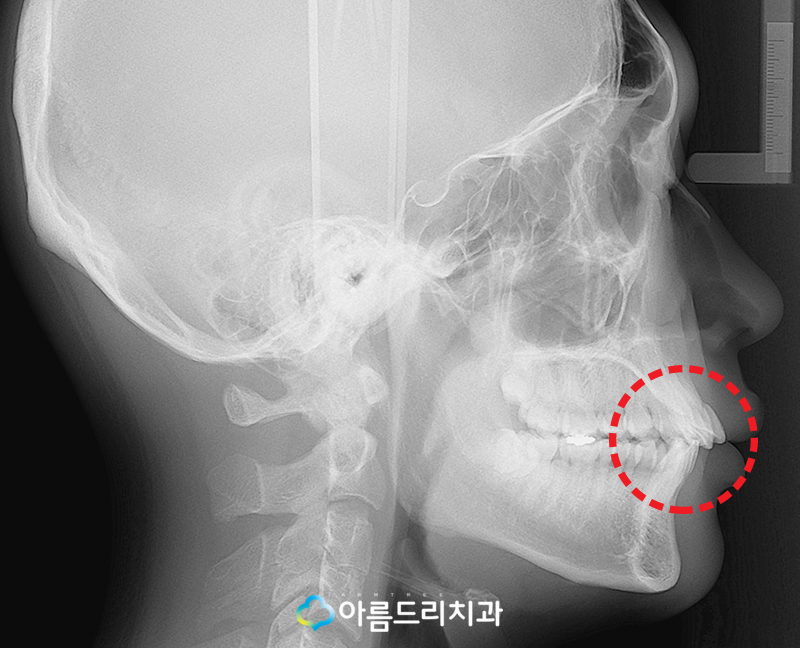

우선 환자의 치아 엑스레이 사진을 확인해 본 결과 상악과 하악의 앞니가 살짝 돌출되어있는 상태를 사진을 통해 확인할 수 있으실텐데요.

아래에 있는 치아 사진을 보면 어떤 치아에 문제가 있는것인지 보다 자세히 알수 있어요.

정면에서 찍은 사진을 보면 가장 눈에 들어 오는 치아는 상악 앞니(11번) 치아가 틀어져 있고 하악 전치(42번) 치아가 안쪽으로 많이 들어가 있는 것을 확인할 수 있었는데요.